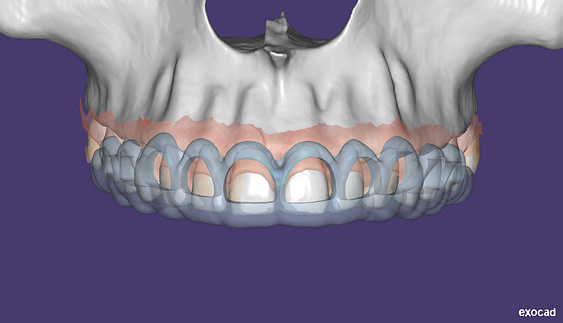

So what is Segmentation? It basically means taking the CBCT and delineating all the different 3D structures, bones, individual teeth, etc.

These can then be individually exported via the software by generating STL files from CBCT dicom data. This can be used in other dental software. Jaw STLs can be used in Modjaw (jaw motion capture) for TMJ analysis, for example. As well as in exocad to help visualize the jaws for surgical planning or guide creation.

- CBCT segmentation

STLs of upper and lower jaws imported into Modjaw for TMJ analysis in jaw motion. this is made possible by CBCT segmentation using Diagnocat.

The surgical crown lengthening guide was made with the aid of maxilla STL to visualize crestal bone level. Again thanks to CBCT segmentation by Diagnocat.